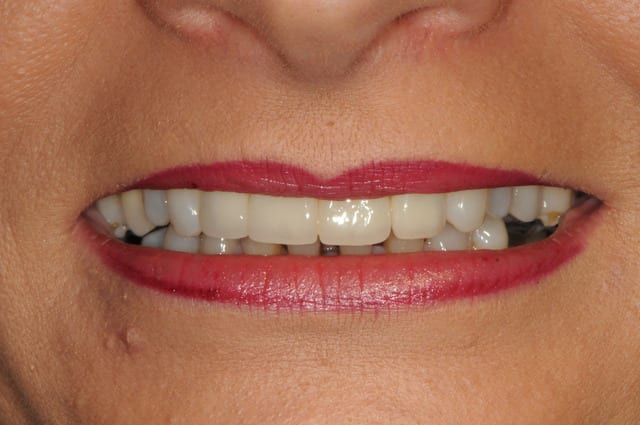

suite et fin .

photos 1 et 2: jour j

photo 3: j+15